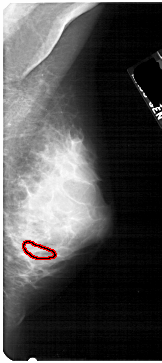

FILE: A_1746_1.RIGHT_MLO.OVERLAY

TOTAL_ABNORMALITIES 1

ABNORMALITY 1

LESION_TYPE CALCIFICATION TYPE PLEOMORPHIC DISTRIBUTION CLUSTERED

ASSESSMENT 4

SUBTLETY 1

PATHOLOGY BENIGN

TOTAL_OUTLINES 1

BOUNDARY